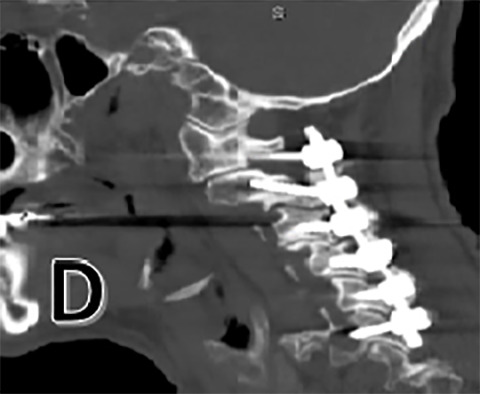

The patient would undergo posterior cervical arthrodesis, or fusion, with instrumented fixation from C1-6 with decompressive laminectomy (removal of the lamina to relieve pressure on the spinal cord and nerves) from C4-6 to treat associated stenosis, or narrowing of the spinal canal. Intraoperative neuromonitoring was utilized along with fluoroscopy for localization and lateral mass screw placement. The authors utilized an arterial line and a large bore 16-gauge intravenous catheter in the antecubital fossa to ensure adequate access for fluids and blood pressure monitoring. No signal changes were noted intraoperatively and patient was successfully extubated.

A post-operative CT scan is provided (Figure 1 D). The patient was placed in the ICU for post-operative monitoring. He tolerated the procedure well and his hospital course was uncomplicated. He was discharged in stable condition for a short course of inpatient rehabilitation.